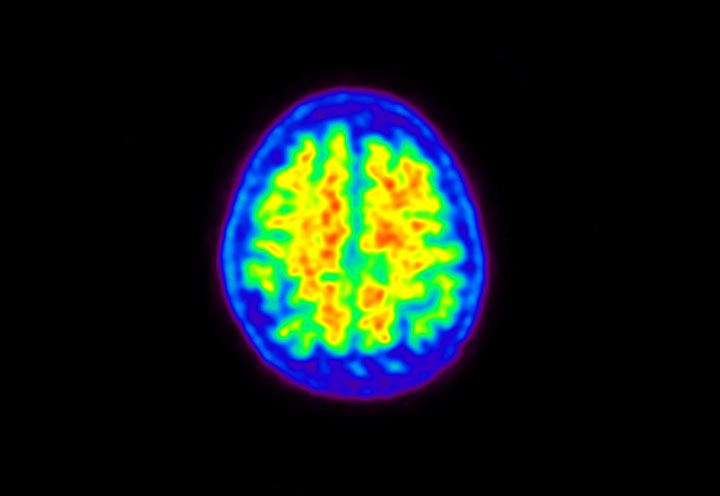

Head / Case5 : Amyloid

Axial

Courtesy : Kindai University Hospital

- Imaging protocol

- Injected dose: 4.27 MBq/kg, 18F-Flutemetamol

- Uptake time: 99 minutes

- Scan time: 20 minutes